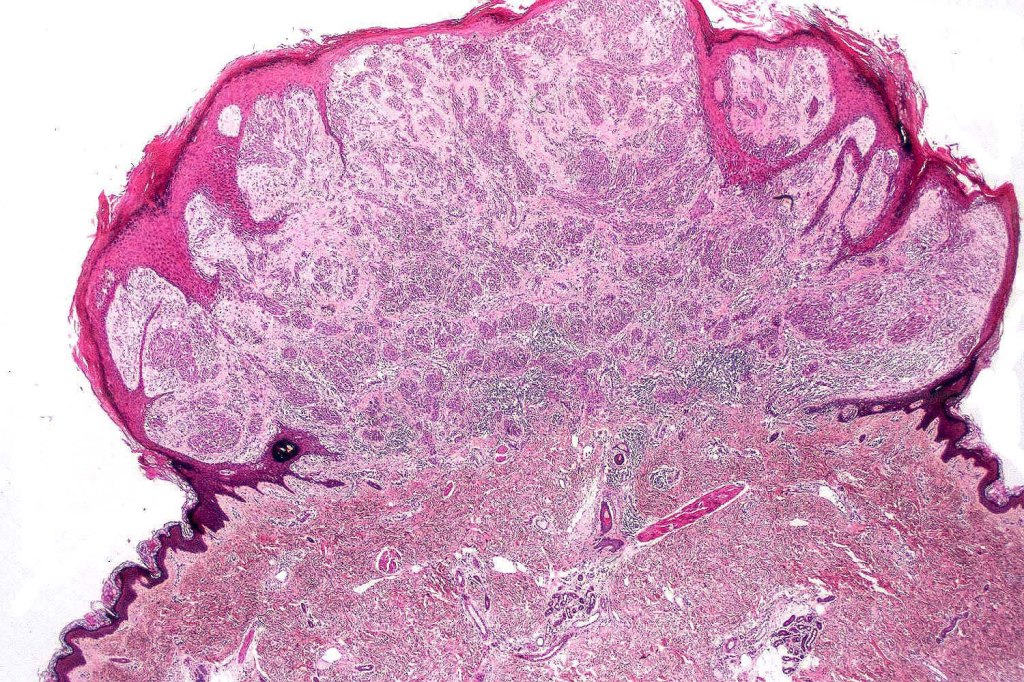

•Sharply circumscribed (begins and ends with a nest), symmetrical dome-shaped lesion. Symmetry is both horizontal and vertical (see image below)

•Wedge-shaped with the base uppermost or sometimes plaque-shaped silhouette

•Matures with depth-often best recognized at scanning/low power magnification & readily confirmed with S100 or MART1

•Maturation implies nest size and cell size diminishing with depth, at the base, the infiltrate may have a single cell infiltrating pattern